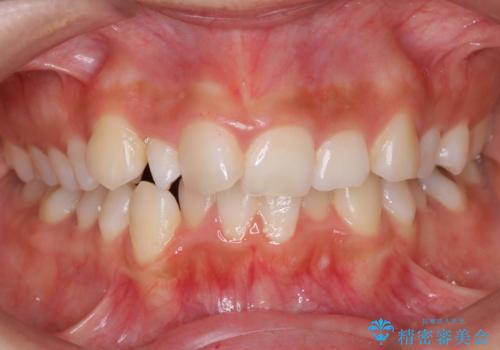

- 前歯のがたつきと出っ歯が気になるとのことで来院されました。

抜歯をして矯正をすることで、前歯を後方に移動させ、ガタガタを改善することができました。